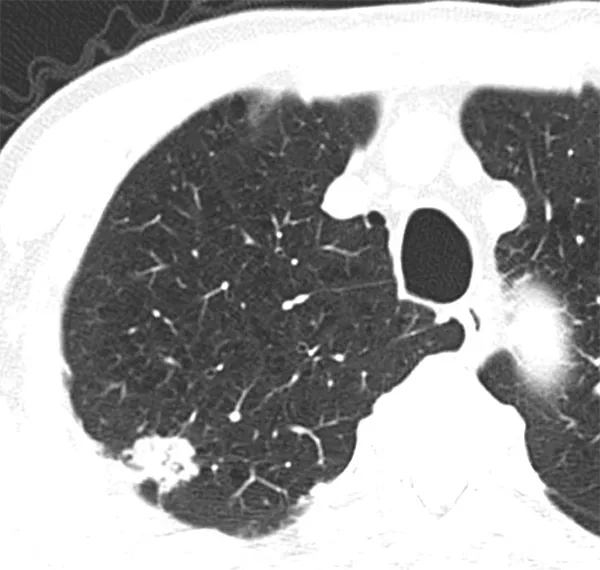

1-1. 筋炎関連間質性肺疾患の画像における検討

皮膚筋炎・多発性筋炎は強皮症、関節リウマチと並んで間質性肺疾患をきたす膠原病である。筋炎関連間質性肺疾患に関しては、最近抗ARS抗体、抗MDA5抗体が簡単に測定できるようになったが、抗ARS抗体症候群はステロイドや免疫抑制薬などが効果的だと言われている一方、抗MDA5抗体陽性間質性肺疾患は急速進行性となる可能性が高いため、速やかにしっかりとした治療を行う必要がある。これらの疾患を診断するためにはまず画像を見てそれらの疾患を疑うことが大切である。これまでに抗ARS抗体症候群における画像の特徴(Waseda Y, et al. European Journal of Radiology. 2016)、抗MDA5抗体陽性間質性肺炎の画像の特徴(Waseda Y, et al. Mod Rheumatol. 2022)を報告し、早期診断、早期加療についての必要性について検討している。